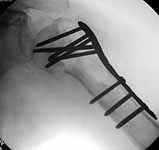

I'd replace it at this point. But if you decide to fix it, i'd use the fixed angled locked screw proximal humerus plate because I think it gives opportunity for many fixed angled points of fixation...more than the single blade for the rod. an example attached (although admittedly not for a nonunion).

steve rabin